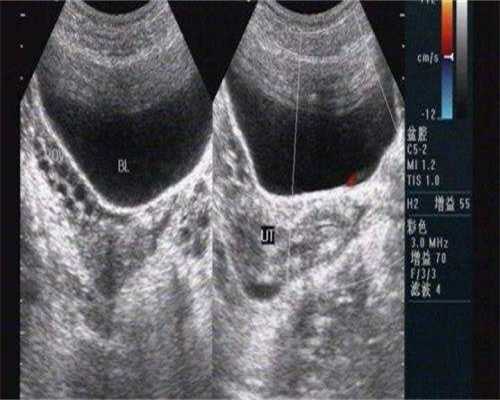

10、你好,许多人对试管婴儿的了解有误,认为是在试管里长大的婴儿。其实,试管婴儿技能是一种手术办法,即从卵巢内取出几个卵子,在试验室里让它们与男方的精子结合,构成胚胎,然后搬运胚胎到子宫内,让胚胎在妈妈的子宫内着床,产生妊娠。别的试管婴儿并非是一种捷径,不能有点问题就去做试管,实际上试管婴儿可不是想做就做、说做就做、有钱就能做的。它并不像咱们幻想的那么容易轻松,经历过的朋友才知道,对女性来说,试管婴儿是一场从身体到心思、从膂力到耐力、从金钱到亲情的极致检测。